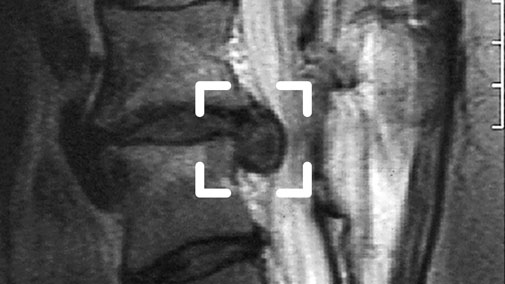

Großer Bandscheibenvorfall L4 / L5 im MRT-Bild.

Das Bandscheibengewebe ist nach hinten in den Wirbelkanal vorgetreten und drückt auf eine Nervenwurzel.